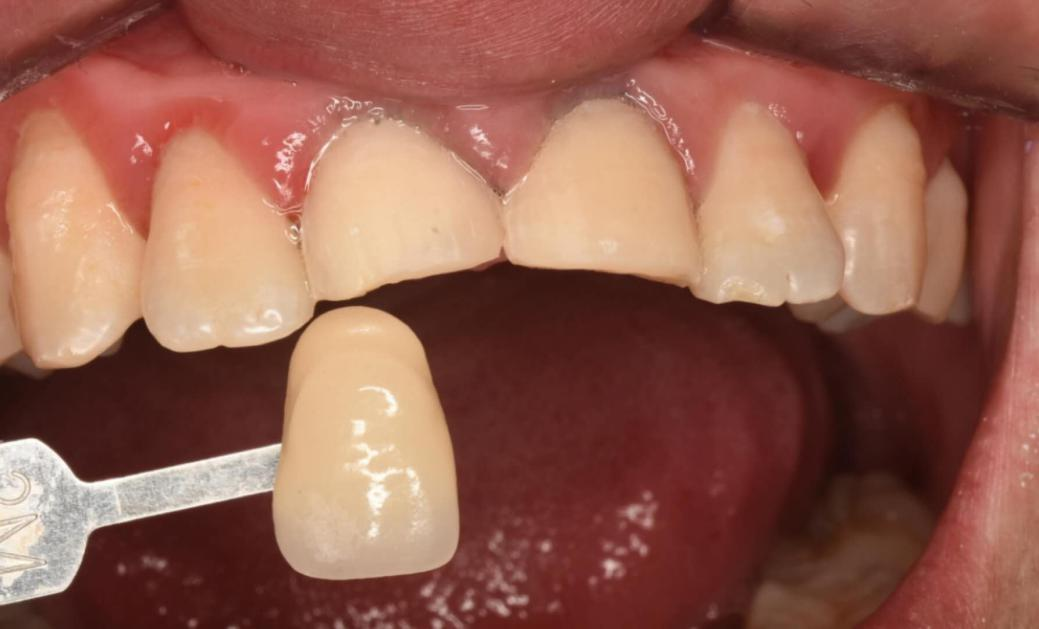

Since only the veneers of the two front teeth need to be made and there is no need to change the color, it is sufficient to compare with the abutment color.